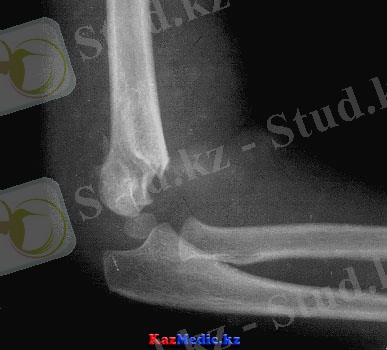

Иық сүйегінің төменгі эпиметафизінің сынуы балаларда иық сүйегінің сынықтарының 64% құрайды, әсіресе айдаршық үсті және айдаршық арқылы өтетін иық сүйектердің сынықтары жиі кездеседі. Айдаршық үстінен өтетін сынықтарда сынық жазығы буынға жетпейді, ал айдаршық аралық өтсе буын ішінде болады да, буын капсуласын зақымдану тауы мүмкін.

Мұндай сынықтар қолды созып немесе шынтақ буынына құлаған кезде пайда болады. Олар сүйек сынықтарының ығысуына байланысты бүгілген немесе жазылған болып бөлінеді.

Клиникасы және диагностикасы . Шынтақ буындағы қозғалыс шектеледі, ауырсыну, ісік, көгеру пайда болады, Гютер сызығы, үшбұрышының теңдігі бұзылады. Диагноз рентгенография жасалғаннан кейін қойылады.

Төменгі эпиметафиздің сынықтары алдыға, артқа, жанына, немесе айлана жылжуы мүмкін. Соған байланысты сынықтар бүгілген, жазылған, айналған болып ажыратылады.

Иық сүйегінің айдаршық үсті сынығы